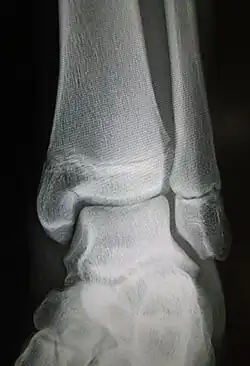

Maisonneuve fracture

| Maisonneuve fracture | |

|---|---|

| Radiograph showing a Maisonneuve fracture of the proximal fibula | |

The Maisonneuve fracture is a spiral fracture of the proximal third of the fibula associated with a tear of the distal tibiofibular syndesmosis and the interosseous membrane. There is an associated fracture of the medial malleolus or rupture of the deep deltoid ligament of the ankle. This type of injury can be difficult to detect.[1][2]